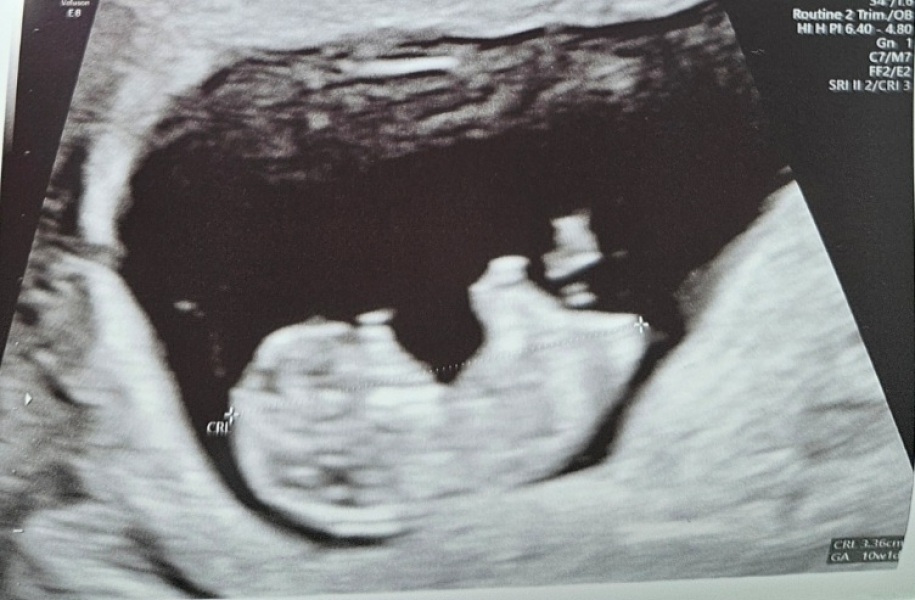

We actually had our NIPT yesterday afternoon. All is well. Baby was moving around and had a very strong heartbeat and measuring exactly at 10+1. We were delighted. Just waiting on the results of the NIPT now 🤞🏻

Aw that’s brilliant 🥰 and must be so reassuring for you to see baby looking healthy after the year you’ve had. It does give me hope it can still happen for me too. So glad all looks good 🥰